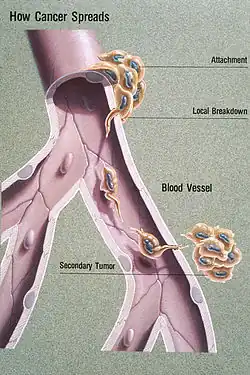

CNS metastasis

Lymphoma cancer types have varying probabilities of metastasizing to the CNS, resulting in secondary CNS lymphoma (SCNSL), which may appear simultaneously as systemic lymphoma, or as remission after systemic lymphoma is treated. Synchronous, or de novo disease is diagnosed in approximately 40% of patients and relapse in 60%.[8] Overall, CNS involvement is observed in 2 to 27% of patients with aggressive systemic non-Hodgkin’s lymphoma.[5] 5% of patients with diffuse large B cell lymphoma, the most common type of non-Hodgkin lymphoma, result in SCNSL but account for most SCNSL cases.[3]

Hypotheses on CNS dissemination include, in order of most to least confirmatory evidence, haematogenous spread, direct extension from adjacent bone marrow infiltration, centripetal growth along neurovascular bundles, or via intervertebral venous plexus. Haematogenous spread entails the migration of lymphoma via blood circulation, and given its abundant blood supply, arrives and penetrates into the CNS, usually involving the cerebrospinal fluid and meninges. Solid parenchymal brain metastasis is more likely to occur in extranodal-originating lymphomas such as the testis.[9]